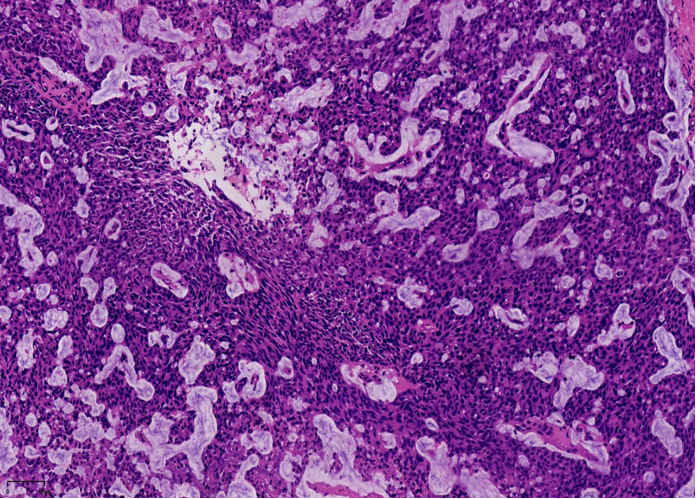

2、实性乳头状癌伴浸润:轮廓圆滑的结节,伴有浸润性成分,包括粘液癌,NET,浸润性癌(NST)

SPC+富于细胞的黏液癌

SPC是从原位癌到浸润癌的连续的形态学谱系。

原位SPC的乳头轴心及导管周边的肌上皮可以存在,也可以不同程度减少。原位SPC可被视为导管原位癌的特殊亚型,因此,临床可以按导管原位癌处理。极端状态下,导管周边的肌上皮可以完全缺失,此时可被称为膨胀性或推挤性浸润,其形态与原位SPC高度相似。研究显示,膨胀性浸润的SPC通常不发生转移,因此仍可按导管原位癌处理。

当在原位SPC的背景上,部分原位SPC轮廓变得不规则,或呈地图、锯齿状,并出现促纤维反应,或浸润脂肪,可称为原位SPC伴浸润(毁损性浸润),这时需按浸润癌处理。